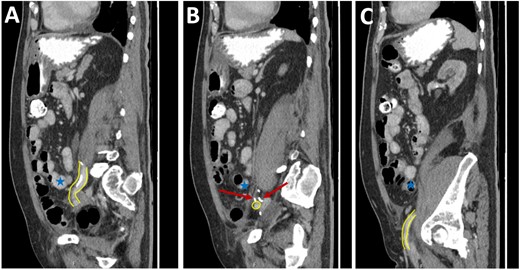

Post-operative CT scan. Series of sagittal images progressing from most medial (image A) to most lateral (image C). The patent EIA has been highlighted in yellow. Surgical clips are noted in image B (red arrow). Normal small bowel is noted in all images (blue stars).